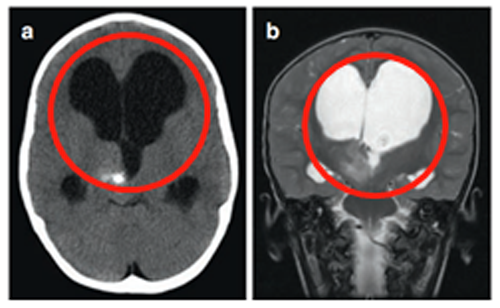

3岁患儿因呕吐和巨脑畸形就诊。CT及MRI检查显示右侧丘脑病变伴钙化及第三脑室后部梗阻,引发脑积水。

在8岁、11岁和13岁时,James T. Rutka教授通过第三脑室内窥镜切开术成功治疗脑积水,影像显示肿瘤增大伴多发囊肿形成,并逐渐出现左上肢震颤。

13岁时进行神经导航和超声引导下活检,确诊为WHO I级毛细胞星形细胞瘤。随着肿瘤囊肿持续扩大,患儿出现急性偏瘫症状。

超声引导下将Ommaya导管和储液囊置入肿瘤囊性部分。术后MRI显示囊性占位解除,脑室形态逐渐恢复正常。四个月后,因偏瘫症状未改善,行经胼胝体半球间入路肿瘤次全切除术。术后偏瘫改善,患儿生长和智力发育正常,近期随访显示肿瘤无复发。免疫组化检测显示RAFV600E突变阴性,H3K27M阴性。